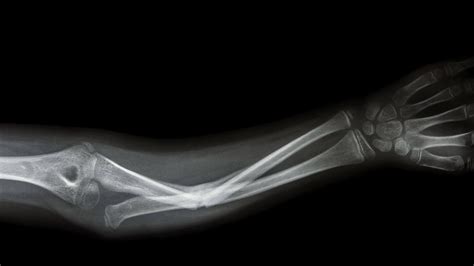

Wrist Fractures

Wrist fractures, often resulting from falls or sports injuries, are common and can be painful. Treatment options include:

• Immobilization with a cast or splint.

• Surgery for severe fractures, such as those involving multiple bones or joints.

• Physical therapy to restore range of motion and strength.